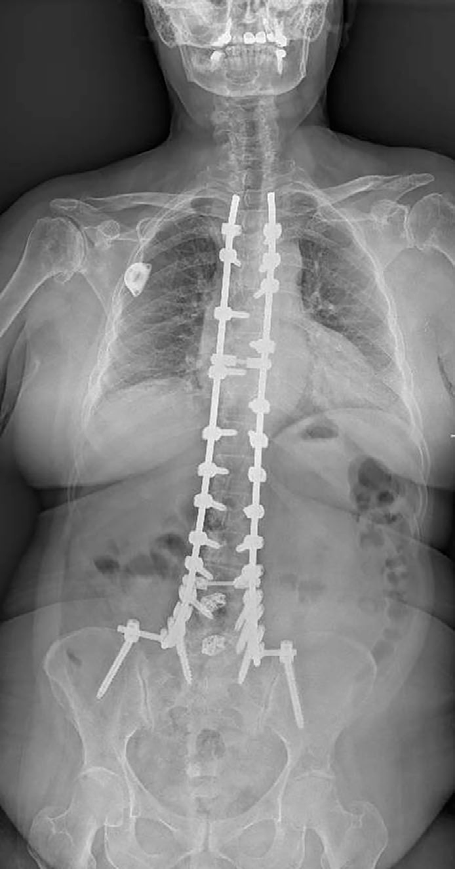

Se realizó cirugía de revisión con foraminotomía y laminectomía L2-L3, laminectomía completa L3-L5 confirmando liberación completa de raíces izquierdas L2 a L5, además de laminectomía T8-T9.

Se revisó a la paciente en consultas donde se observó mejoría significativa, restauración de la bipedestación, movilidad conservada en ambos MMII, recuperando la extensión activa de la rodilla izquierda y realizando vida independiente antes del año postquirúrgico.